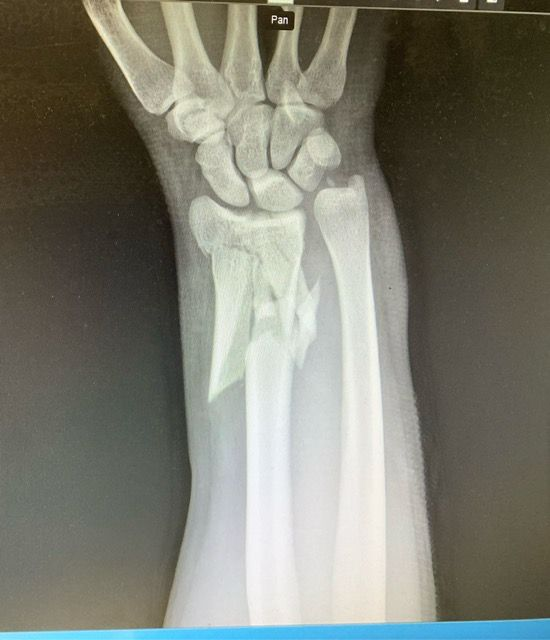

Traumatologia adulta e pediatrica

La traumatologia rappresenta un ambito fondamentale dell’attività specialistica, rivestendo un ruolo cruciale nella cura e nella riabilitazione dei pazienti colpiti da eventi traumatici. La gestione delle

lesioni traumatiche dell’apparato muscolo-scheletrico si estende a una vasta gamma di condizioni, che comprendono traumi articolari, fratture di varia gravità e lesioni che interessano sia gli arti superiori che quelli inferiori. Grazie a un’esperienza ospedaliera consolidata, i professionisti sono in grado di affrontare non solo le urgenze traumatiche, che richiedono un intervento rapido e preciso, ma anche la gestione degli esiti post-traumatici, ponendo particolare attenzione al recupero funzionale e al miglioramento della qualità della vita dei pazienti. L'approccio multidisciplinare e l'uso di tecnologie avanzate sono cruciali per garantire risultati ottimali.